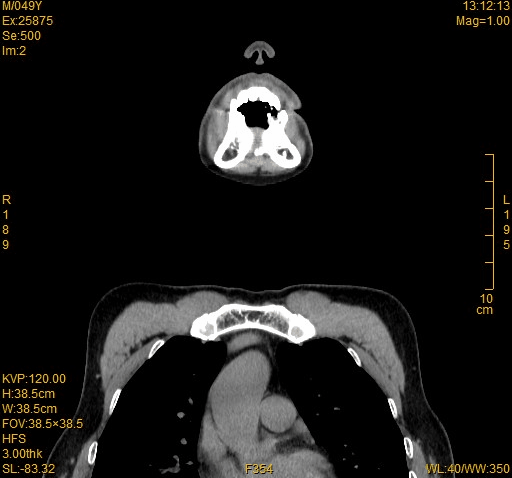

食管异物阻塞最典型的临床表现为突发的吞咽困难、异物感和疼痛感。发生食管异物阻塞后,患者通常能够回忆病史并描述胸部疼痛不适和吞咽困难等症状,根据病史和临床表现可以进行初步判断。内镜检查是诊断食管异物的最重要手段,对于怀疑食管异物阻塞的患者,通过内镜检查即能明确诊断。CT检查对于食管异物的诊断同样有很高的价值,是首选影像学检查方法,CT检查主要以评估异物的位置、大小、形状以及是否存在穿孔。关于检查的相对禁忌症:由于食管造影剂会附着在异物及食管黏膜上,干扰内镜的视野,耽误内镜检查的时间,且存在误吸的风险,不建议使用。怀疑食管穿孔的患者禁忌行钡剂食管造影。

一般吃东西卡出,来得都比较着急,首先急诊会挂耳鼻喉科。对于颈部食管异物的患者,根据情况进行颈部CT和喉镜检查,判断是否有异物以及异物停留的位置。如果异物较小,有条件时应首先考虑在喉镜下进行异物取出。对于异物位置较深的患者,则需要行胸部CT和胃镜检查,有条件的情况下首先考虑在胃镜下进行异物取出。对于情况较为复杂的食管异物,比如异物时间较长或嵌顿较深,已引起食管穿孔或食管周围脓肿等并发症,就需要在全身麻醉下经胃镜取出,这时胸外科医生需要随时待命,一旦出现意外情况立即行开胸手术。